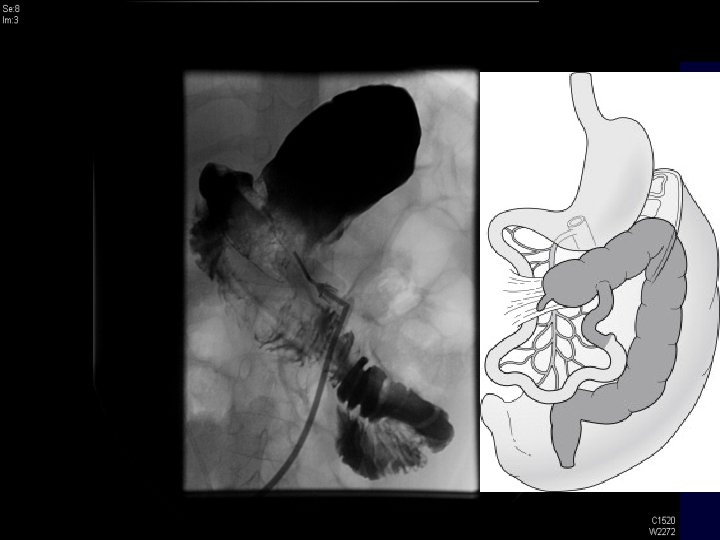

UGI Series: • MALROTATION • PROXIMAL SMALL BOWEL WITH ABNORMAL POSITION OF THE DUODENAL JEJUNAL JUNCTION AND NO EVIDENCE OF OBSTRUCTION.

pediatric